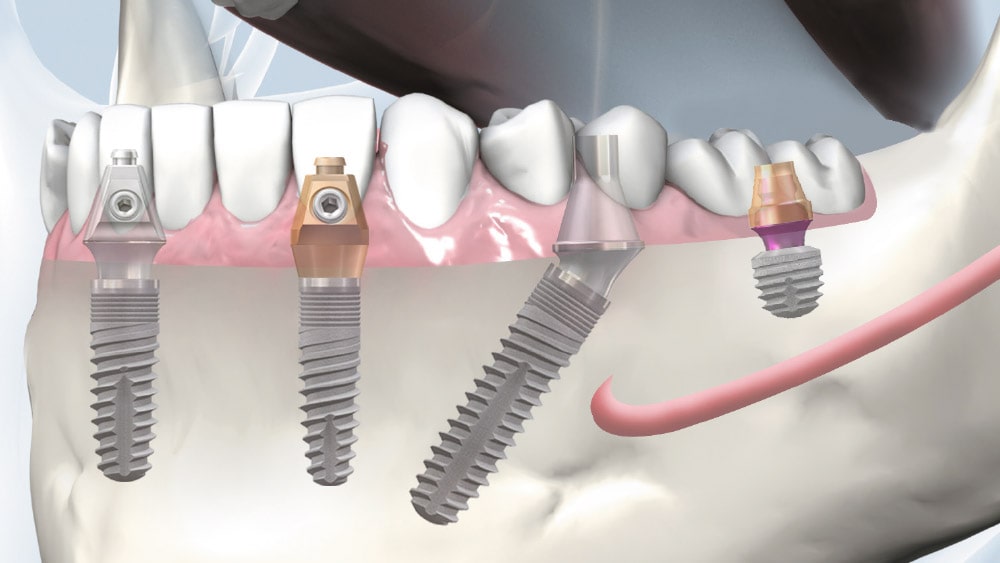

copaSKY köprü abutmentı, çekici olmayan bir abutmenttır. Düz konik bağlantı, iki implant arasında 20°’lik bir angulasyonun dengelenmesini sağlar. Bu nedenle çoğu köprü, diş laboratuvarında simante edilebilir.

Restorasyon kolayca birleştirilebilir ve oklüzal vidalarla sabitlenebilir. Uzun konik bağlantı, lateral ve oklüzal kuvvetleri doğrudan üst yapıdan implanta aktarmaktadır. Bu nedenle vida, gevşeme ve kırılmaya karşı korunur.